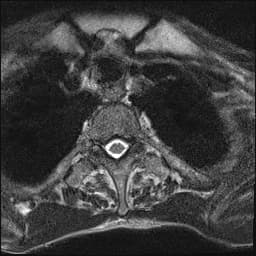

Cộng hưởng từ (MRI)

MRI là phương tiện hình ảnh ưu tiên để phân giai đoạn tại chỗ ung thư cổ tử cung do độ phân giải mô mềm vượt trội và khả năng tạo ảnh đa mặt phẳng. Cổ tử cung bình thường trên ảnh cộng hưởng T2 gồm ống cổ tử cung sáng và vành sợi xơ cổ tử cung tối. Trong ung thư cổ tử cung, khối u thường hiện diện như một khối có tín hiệu trung bình đến sáng trên ảnh T2, thay thế vành sợi xơ cổ tử cung vốn tối [1]. Sự tương phản này giúp xác định rõ ranh giới khối u.

Trên ảnh T1, khối u thường đẳng tín hiệu so với cơ tử cung và không tăng đậm rõ nếu không tiêm thuốc. Các chuỗi T1 ức chế mỡ hữu ích để phát hiện xâm lấn mạc rộng và đánh giá xâm lấn thành chậu. Trên ảnh T1 sau tiêm thuốc cản quang, khối u tăng đậm không đồng đều do hoại tử.

Chụp khuếch tán (DWI) rất nhạy để phát hiện mô ung thư, với ung thư cổ tử cung thường cho thấy khuếch tán bị hạn chế, sáng trên ảnh b-value cao và tối trên bản đồ ADC. Đặc điểm này giúp phân biệt khối u với mô xơ hóa hoặc tổn thương sau điều trị.

Ảnh cộng hưởng T2 theo mặt phẳng dọc cung cấp hình ảnh tối ưu về kích thước khối u và mối liên hệ với ống cổ tử cung và thân tử cung. Ảnh T2 mặt ngang và mặt ngang giúp đánh giá xâm lấn mạc rộng, xác định bằng dấu hiệu mất vành sợi xơ cổ tử cung và khối u lan không đều vào mô mỡ mạc rộng. Dấu hiệu "vuốt" (claw sign) — mép khối u tua tủa, kéo mô xung quanh — gợi ý xâm lấn sâu.